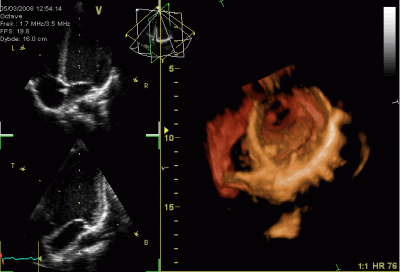

دکتر افسون فضلی نژاد

دانشیار فلوشیپ اکوکاردیوگرافی